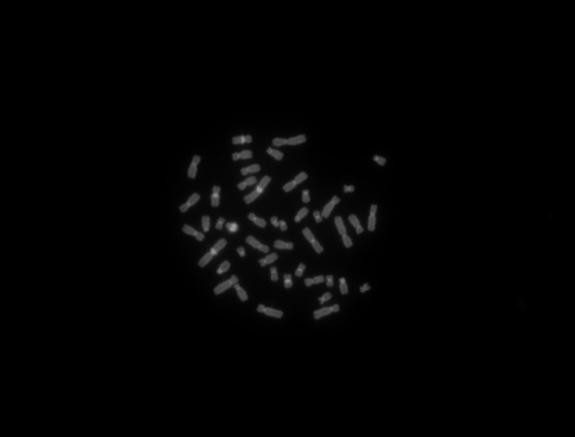

熒光圖像:

熒光C帶2

Y微缺失DAPI藍紫

5、應用實例:明場下,畫質十分細膩,完全能滿足一般應用。軟件具備,亮度,對比度,伽馬的參數(shù)的調(diào)整,通過調(diào)節(jié),都能得到比較滿意的照片。色彩還原方面稍顯不足,對于黑色的還原不是很理想,往往是有些發(fā)綠。熒光方面表現(xiàn)也很好,熒光模式下背景足夠黑暗,沒有明顯的噪點信號,彩色拍攝模式下,對紅色和綠色熒光的色彩還原準卻,但是對藍紫色和天藍色熒光的還原有待加強。建議拍攝熒光用單色模式,然后添加偽彩,熒光疊加。所以建議廠家增加這兩個功能。